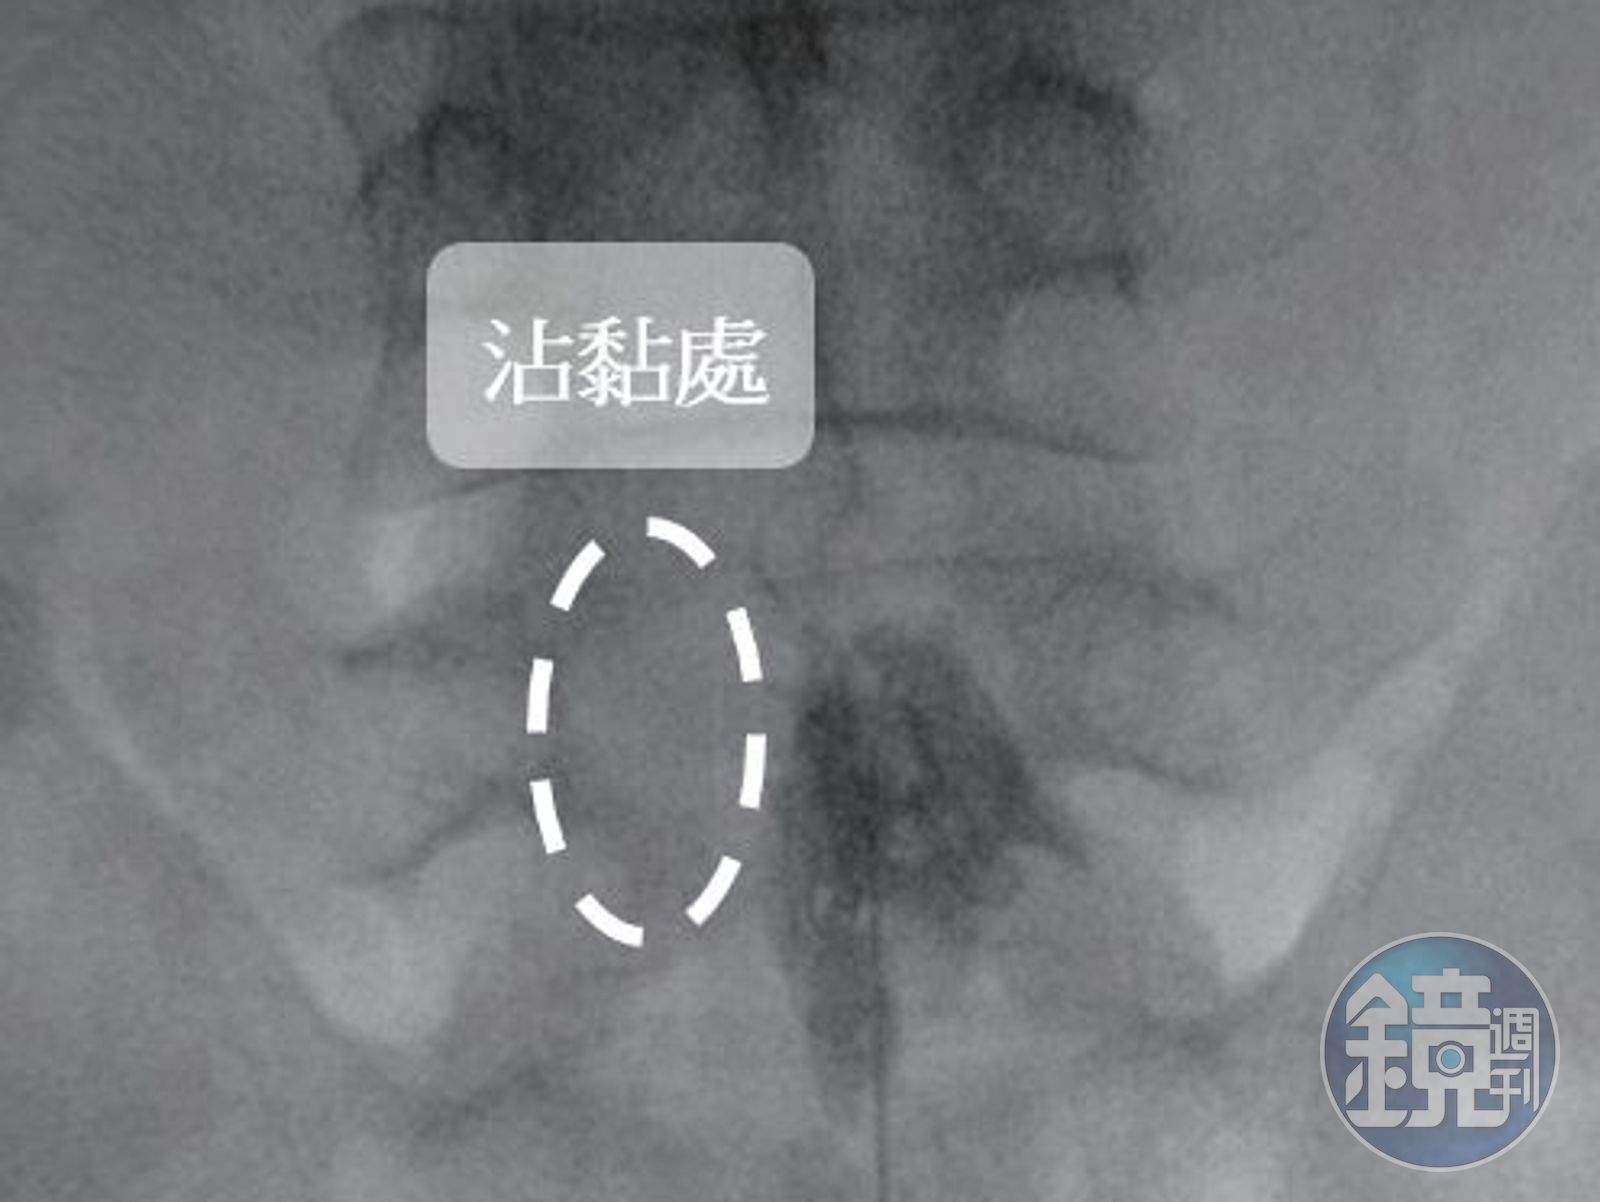

許安智說明,「硬脊膜外神經解沾黏術」利用X光機進行定位操作,會從靠近尾椎的薦椎裂孔先施以局部麻醉藥物並導入導管,再注入顯影劑分辨出沾黏處,接著針對沾黏處利用輕微剝離的方法將神經分離出來,減輕神經因沾黏造成的壓迫,最後注射消炎的藥物減緩疼痛。